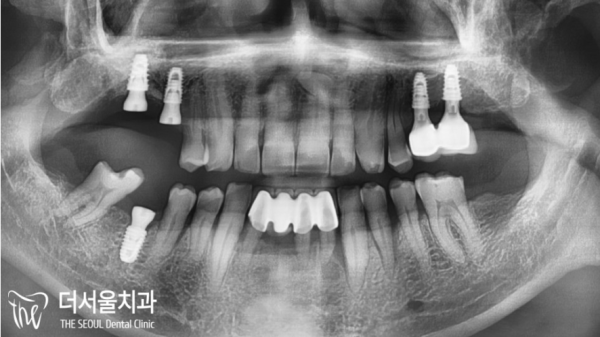

우선 정확한 진단을 위해 파노라마 사진을 찍어보기로 했습니다.

저희 태평역치과 더서울치과는 환자분의 정확한 진단을 통해 구체적인

치료 계획을 수립하여 안전하고 정확하게 치료를 해 드리고 있습니다!

골소실이 심하여 바로 수술이 불가하다는 결론입니다.

때문에 상악동거상술을 통해 뼈이식을 진행하여 모자란 골을 채워주기로합니다.

그 이후에 임플란트가 진행될예정입니다.

여러차례 골이식을 통해 픽스쳐를 심을 수 있었습니다.

안정적으로 픽스쳐가 잘 고정되어있는것을 확인했습니다.

치료후의 모습입니다. 상악이 완전히 바뀐것을 확인할 수 있습니다.

이제 안정적인 어금니로 편안하게 식사를 하실 수 있게 되었습니다.